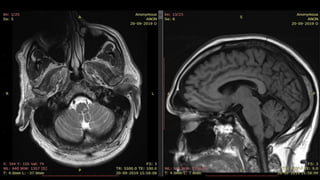

• #21 Here is an example. T2 axial and T1 Saggital image show focal altered signal intensity area on the left side of the medulla appearing hyperintense on T2 and hypointense on T1

• #38 Here is the T1 SAGITTAL image of a patient showing hypointensity in right FRONTOPARIETAL REGION

• #40 Here is the T2 Axial image of the same patient showing hyperintensity in right FRONTOPARIETAL REGION WITH BLURRING OF GREY WHITE MATTER JUNCTION

• #41 FLAIR CORONAL images show HYPERintensitY in RIGHT FRONTOPARIETAL REGION